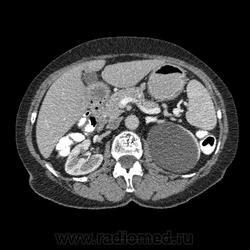

Впечатление, что дуля эта вне головки п.ж., интрамурально в луковице, что ли... тогда возможно GIST, но надо дайком. Утолщение подслизистой в антральном отделе желудка, не удается проследить переход от желудка к 12-перстной((. Внутрипросветно/внутристеночно - не разобрать. 1 фаза?

Клинику! Есть ли признаки высокой тонкокишечной непроходимости, что при ФЭГДС в 12-перстной - туда удалось пройти или нет? ААА! Одни вопросы))))

В-общем, варианты такие без дайкомов: пролапс слизистой в 12перстную, безоар, внутрипросветный дивертикул, гастроинтерстинальная опухоль. И большие сомнения, что это в головке п.ж. - оно отделено от неё тонким слоем жировой клетчатки

Фаз было 3. Видео не выставлял прошлый раз пришел ответ из сайта что видео не работает на сайте Идет накопление контраста в нативе в центре +2+4 по периферии +32+34 .в артериальную +20 и +65 +70 соответственно.

Что оно копит - бог с ним... если это пролапс слизистой, то суммация стенок. Безоар бы не копил. Напрягает отек слизистой в антрале... Это должно быть скорее внутри просвета кишки, т.к. оттесняет газ в 12-перстной на периферию. Без дайкомов больше ничем не могу, извините. Подождём мнения коллег.

Как мне видится - пролапс слизистой желудка в 12-перстную. А мнения коллег что-то нетути...

А что растет из левой почки? Может оно же и желудок сдавливает?

Это расширение всей 12- перстной кишки (стаз).